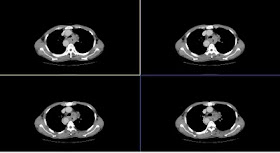

persistent inferior paraspinal mass

located in posterior basal segment

Intralobar sequestration 多於 extralobar

left side 多於 right

feeding by thoracic aorta, pulmonary venous drainage

與 extralobar sequestration (drain 到 systemic vein) 區分。